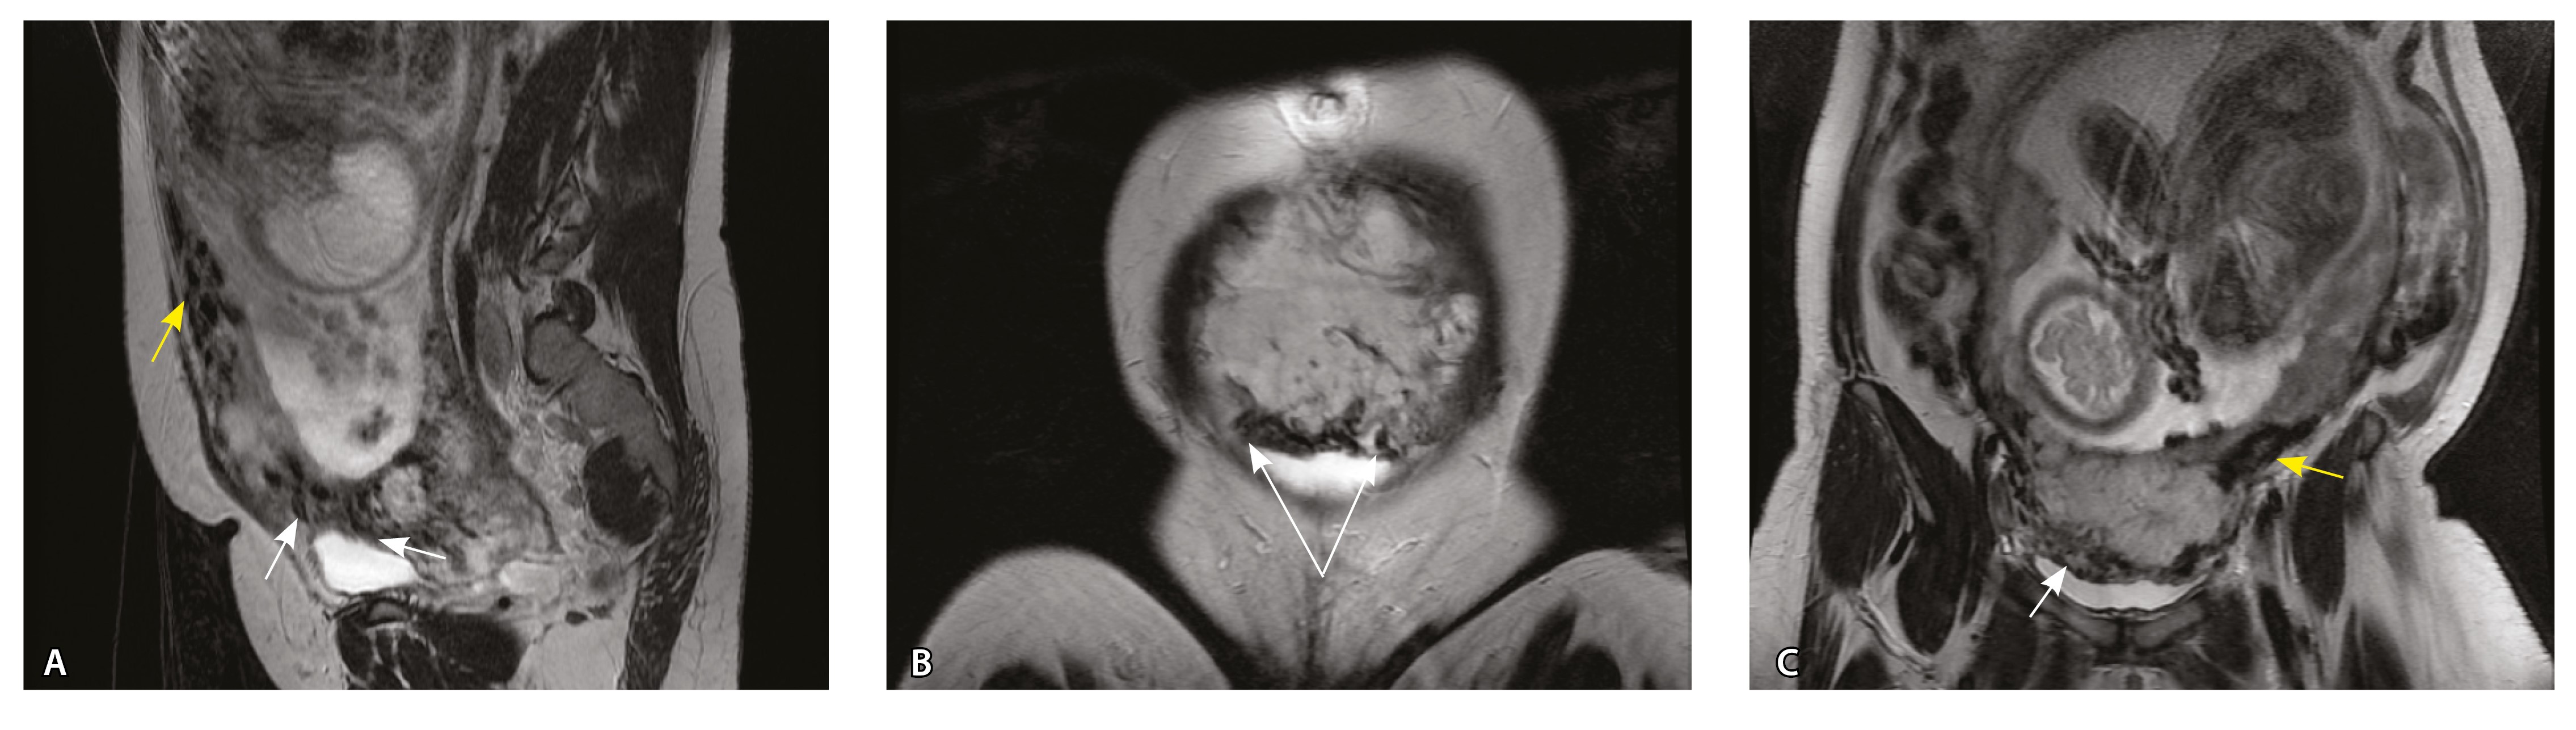

Сосуды 4-го типа. Наличие крупных извитых анастомозирующих сосудов, преимущественно по поверхности матки (в составе серозной оболочки матки) в сочетании с выраженным истончением нижнего сегмента матки (рис. 10).

Рис. 10. Беременность 33 недели, pl. percreta, PAS 3a по FIGO. На магнитно-резонансных томограммах в режиме Т2-взвешенного изображения в сагиттальной (A) и фронтальной (Б, В) плоскостях определяется внутриматочная гиперваскуляризация (желтые стрелки) и гиперваскуляризация в области выраженно истонченного нижнего маточного сегмента, с наличием многочисленных анастомозирующих сосудов по поверхности матки (белые стрелки); стенка матки в данной области представлена ретроплацентарными сосудами

Главным отличием крупных сосудов в составе серозной оболочки является то, что морфологически они находятся в пределах стенки матки. Об этом свидетельствует наличие в операционном материале тонкого поверхностного слоя мезотелия, отделяющего матку от брюшной полости (рис. 11). Его невозможно визуализировать методом МРТ из-за особенностей метода и толщины получаемых срезов.

Рис. 11. Сосуды 4-го типа при гиперваскуляризации стенки матки при патологической инвазии: А – крупный сосуд в составе серозной оболочки матки: справа видны единичные цитотрофобластические клетки (стрелки), не достигающие стенки артерии (иммуногистохимическое исследование, маркер цитокератин 8; × 50); Б – крупные сосуды в составе серозной оболочки: наличие внутреннего слоя эндотелиоцитов (иммуногистохимическое исследование, маркер СD34; × 50)

На микропрепаратах васкуляризация серозной оболочки представлена множеством крупных сосудов, идущих в разных направлениях и анастомозирующих друг с другом. Возможно, имеются артериовенозные соустья. На серийных срезах также видно, что в стенках артерий трудно различимы два слоя миоцитов (продольный и поперечный). Со стороны адвентиции они окружены толстым «футляром» из грубоволокнистой голубой ткани (при окраске по Маллори). Она проникает в стенку артерий, замещая мышечный слой (рис. 12).